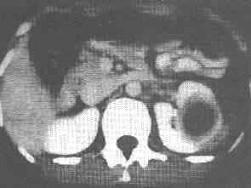

问题 肾皮质多发性脓肿区别急性肾盂肾炎的是前者有 ( )

选项 A、血象白细胞增多,中性高 B、腰部剧痛 C、B超、CT检查肾皮质的占位性病变 D、肾区明显压痛和叩击痛 E、畏寒、寒战、高热

答案 C